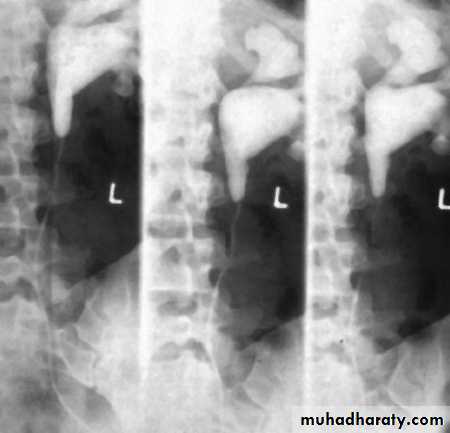

*Ectopic left kidney:-ureter is short (small arrow)